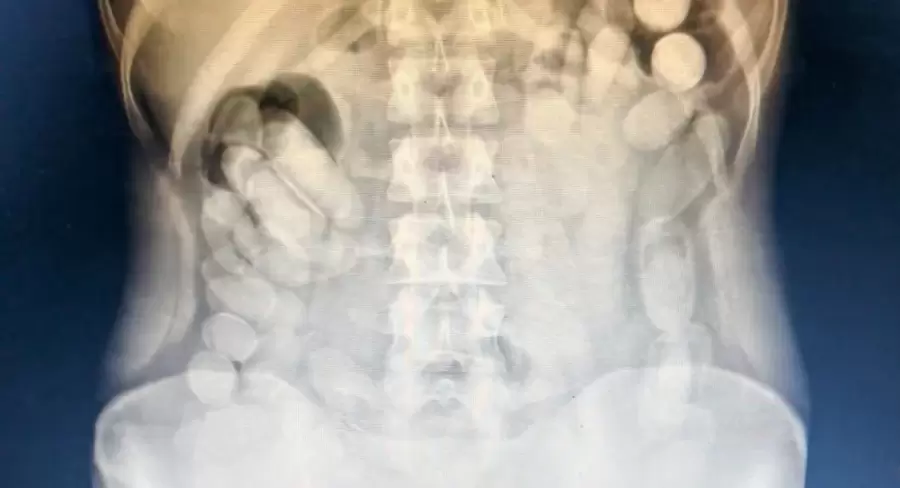

Capsulas de cocaína/ Fuente: Gendarmería

En el hospital, le realizaron estudios médicos que confirmaron la presencia de cuerpos extraños en su abdomen. Horas más tarde, la ciudadana evacuó un total de 106 cápsulas.

En total, se contabilizaron 118 cápsulas con cocaína, con un peso neto de 1 kilo 388 gramos. El Narcotest confirmó que la sustancia era clorhidrato de cocaína.